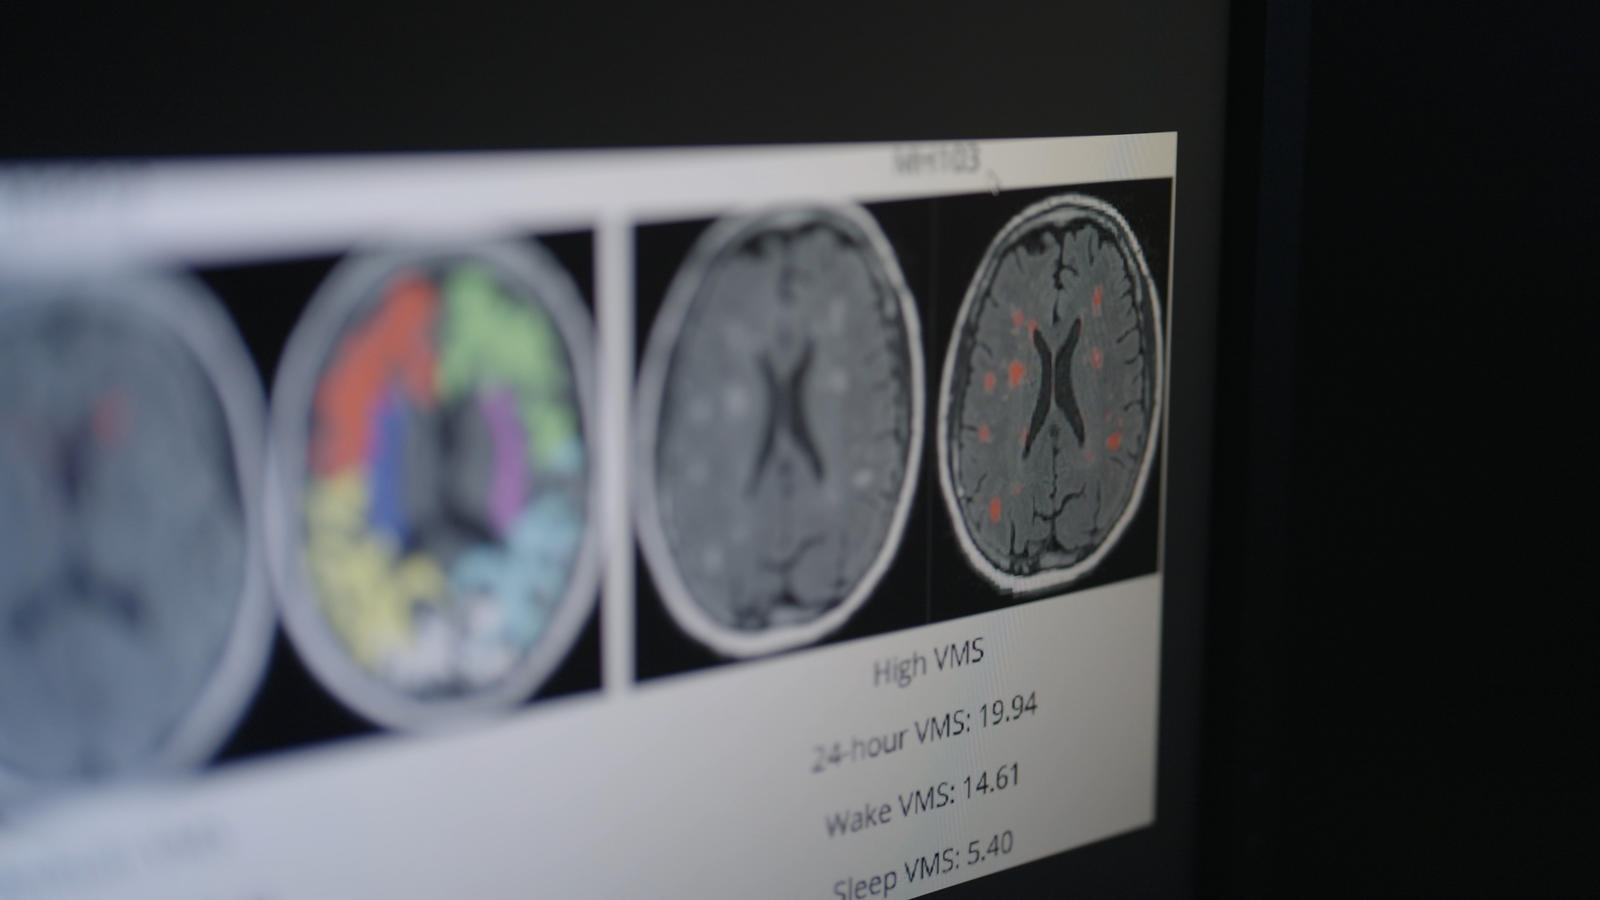

Nun suchen Forschende weltweit nach Antworten, um die Auswirkungen des Östrogenrückgangs auf Körper und Gehirn zu ergründen.

Warum haben vier von fünf Frauen Hitzewallungen, mehr als ein Viertel Schlafstörungen? Warum leiden 41 Prozent unter Gedächtnisproblemen? Warum hat die Altersgruppe 45 bis 54 Jahre die höchste Selbstmordrate ? Wie hängen Menopause-Symptome mit dem dreifach höheren Alzheimer-Risiko von Frauen und Depressionen

zusammen? Welche Möglichkeiten gibt es, dem entgegen zu wirken?